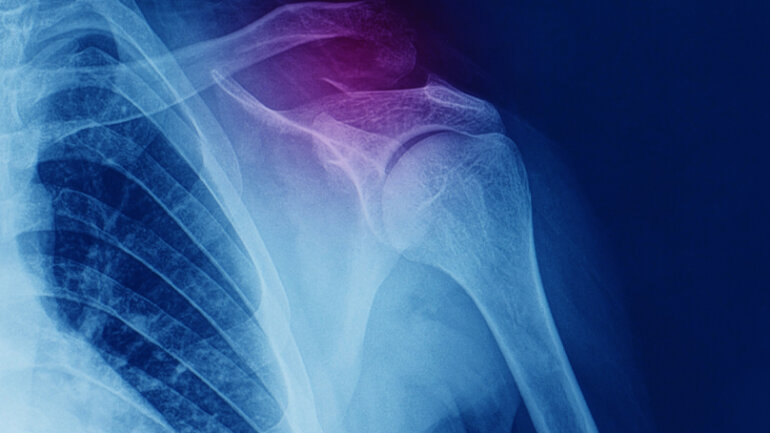

Οι επιζώντες των περισσότερων τύπων καρκίνου διέτρεχαν αυξημένο κίνδυνο κατάγματος οστών για αρκετά χρόνια μετά τον καρκίνο.